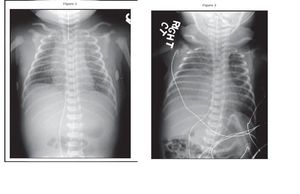

A full-term female infant with a birthweight of 3.5 kg was delivered by caesarean section. Physical examination findings were normal. Four hours after delivery, the infant developed progressively worsening respiratory distress requiring intubation and assisted ventilation. Diagnostic workup confirmed group B Streptococcus (GBS) sepsis and pneumonia. Chest radiography was performed (Figure 1). The infant’s condition gradually improved in the subsequent days and she underwent extubation on the 8th day after birth. However, increasing respiratory distress necessitated assisted ventilation 7 hours later. Chest radiograph obtained after intubation is presented in Figure 2. The findings shown in Figure 2 were unchanged 2 days later. Of the following, the MOST appropriate next step in the care of the infant in the vignette is: A. chest computed tomography B. chest physical therapy C. chest ultrasonography D. fluoroscopy E. thoracentesis